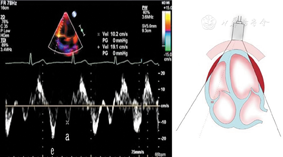

图11

标准心尖四腔切面引导脉冲波多普勒取样二尖瓣口舒张期跨瓣血流速度峰值E峰和A峰、A峰持续时间以及E峰减速时间测量方法